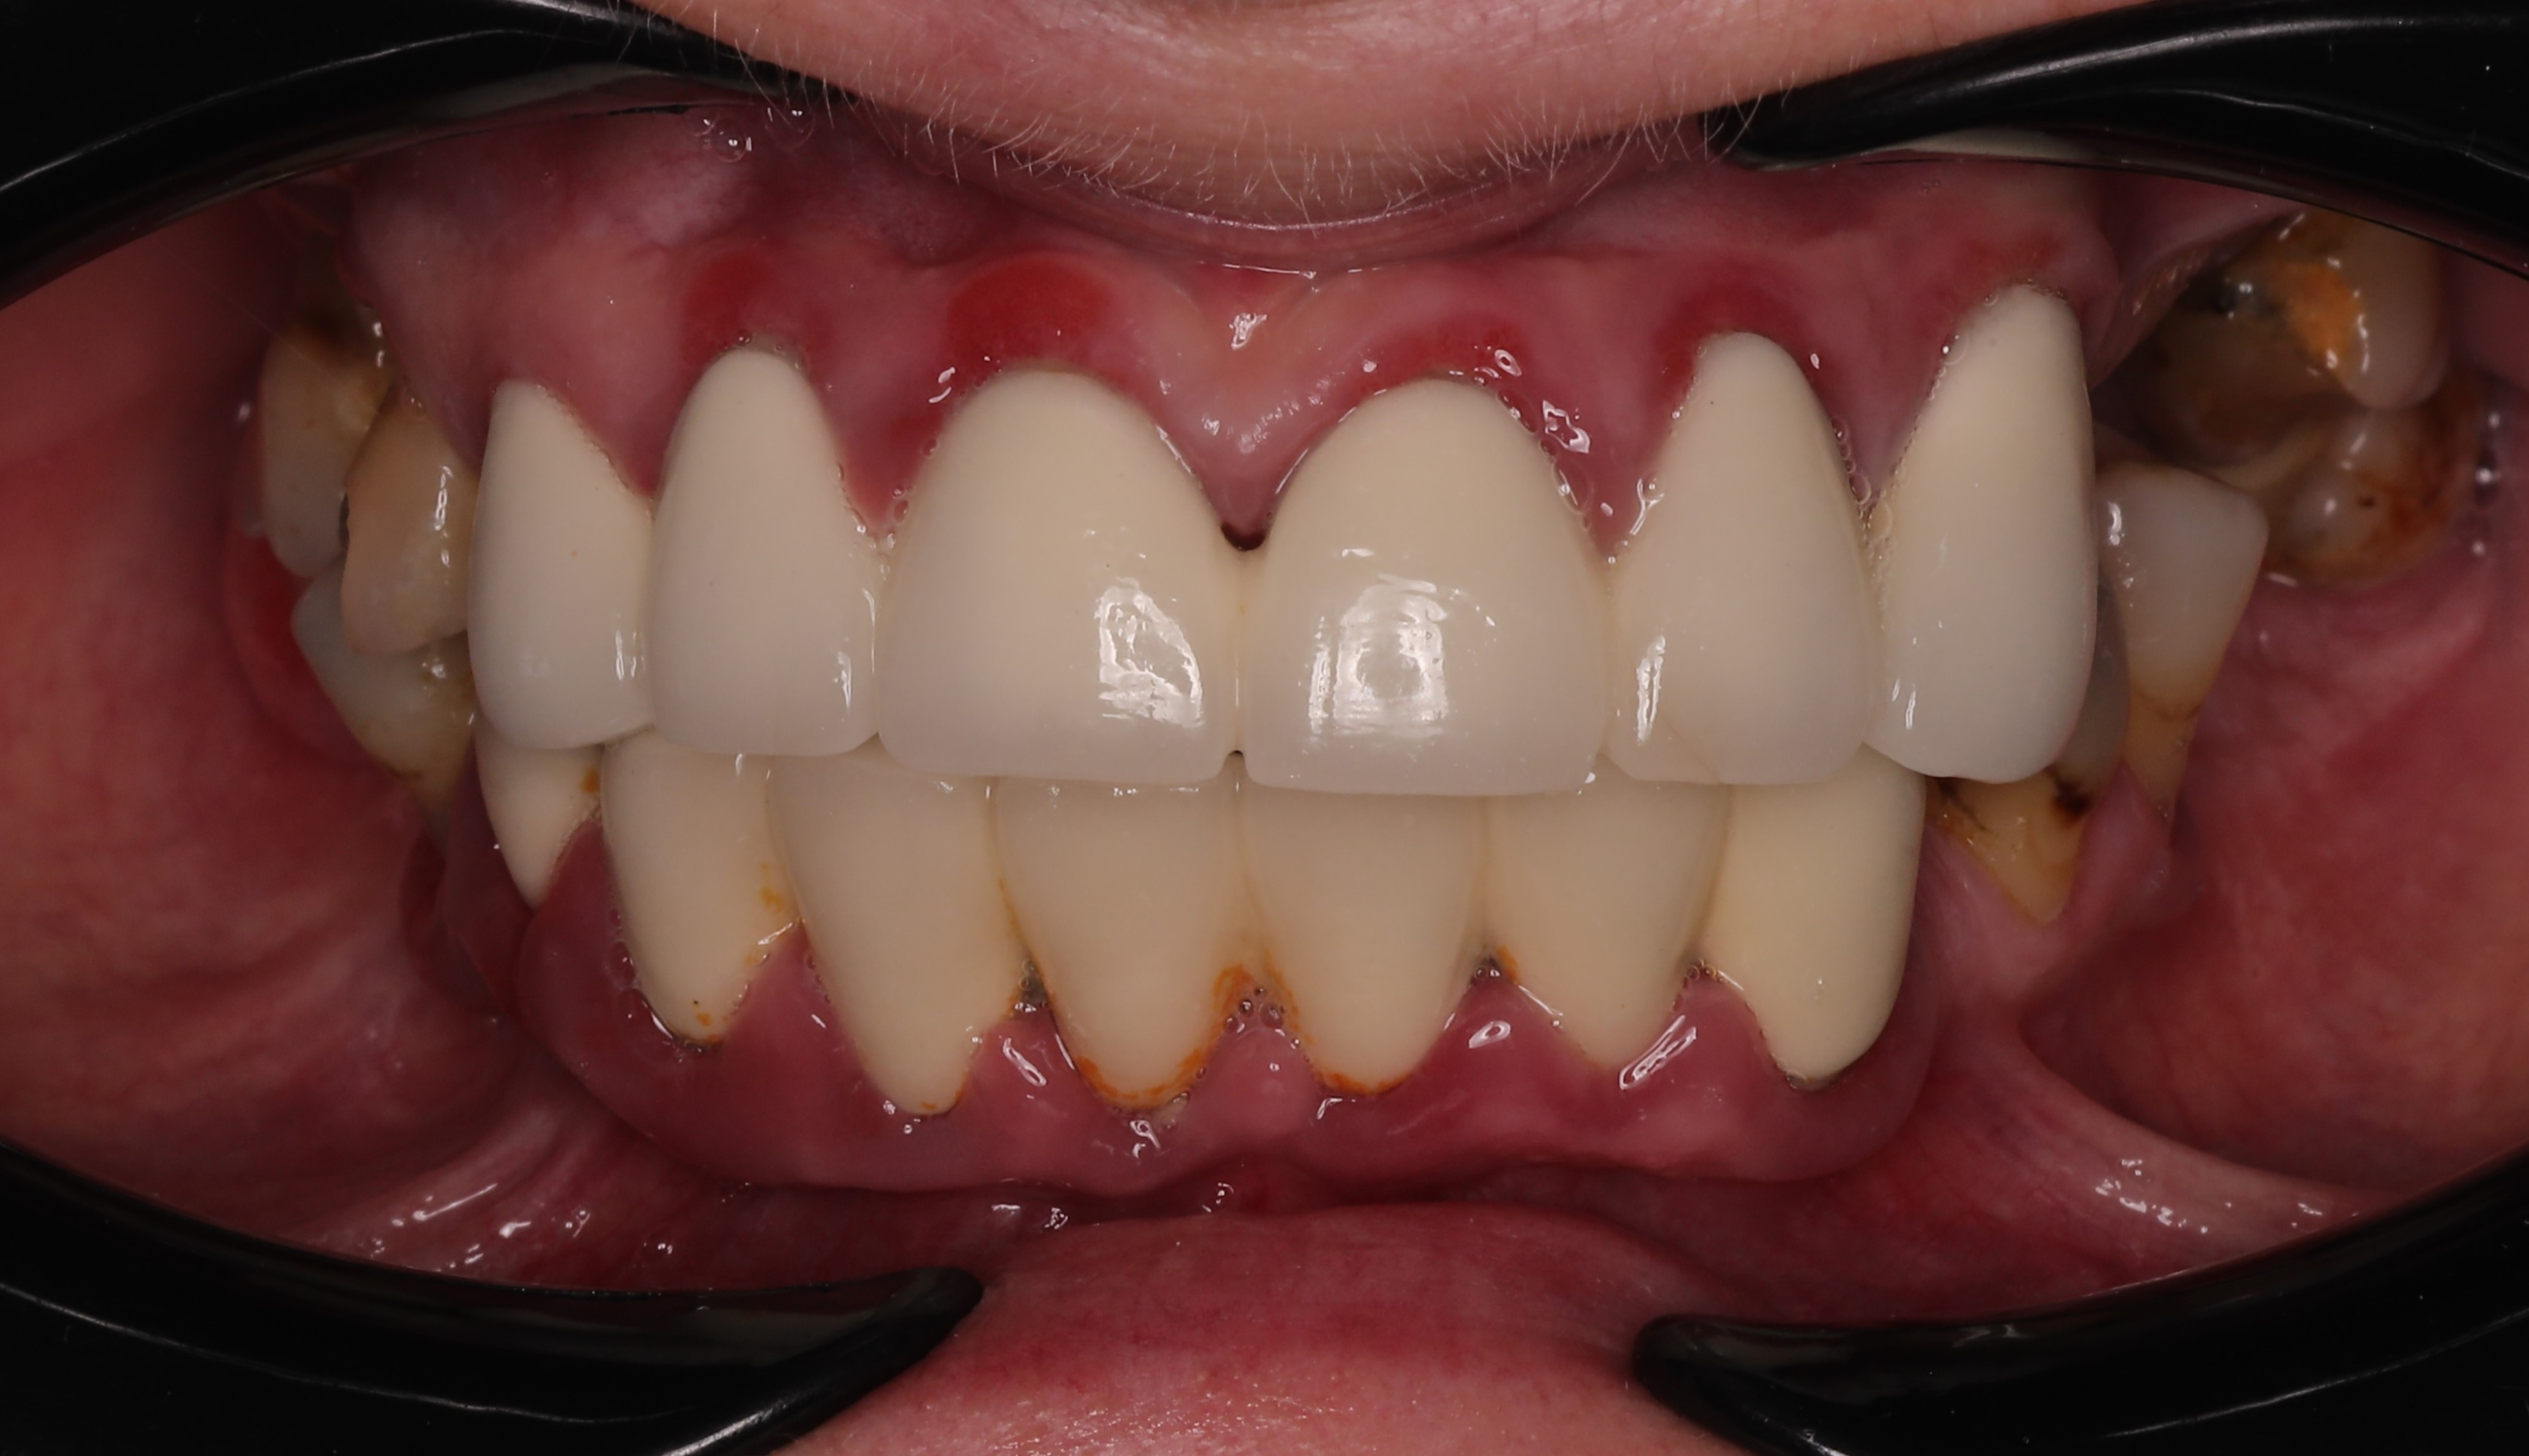

At the six-month follow-up, the patient reported high satisfaction with the functional and aesthetic performance of the provisional restorations. Clinical examination following the removal of the provisionals revealed optimal soft tissue healing and well-preserved gingival architecture. Notably, the Root Shield sites at 13, 12, and 23 successfully maintained the buccal ridge contour, while radiographic evaluation (OPTG) confirmed complete osseointegration of all implants, including the pterygoid fixtures at sites 17 and 27.

The final restorative phase utilized a repeat IPG scan to ensure micron-level accuracy for the definitive frameworks. The maxilla was restored with a zirconia bridge on a titanium framework, while a metal-composite framework was selected for the mandible. The definitive prostheses achieved a perfect passive fit and optimal seating, successfully restoring both masticatory function and the patient’s natural aesthetic smile.